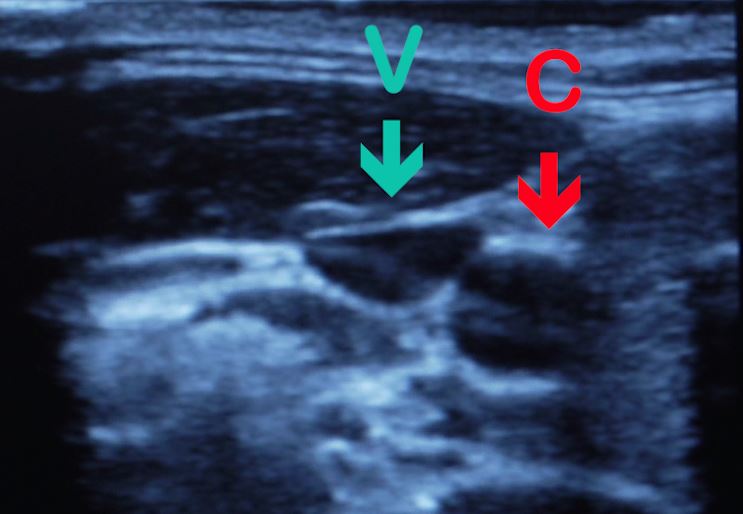

- Přiložte sondu na dříve pohmatem určené místo, kolmo k předpokládané poloze tepny. Tepna se zobrazí jako tmavý kruhový pulsující objekt. Podobně se zobrazí také žíla. Pro odlišení mírně zatlačte na sondu. Krční tepna, ve které krev proudí pod tlakem, zůstane kruhová a pulsující, žíla se deformuje (zplošťuje).

- Na obrazovce se zobrazí zelený křížek. Ten umístěte pomocí trackballu na okraj zobrazené tepny, stiskněte tlačítko Set, následně umístěte bod na protější stranu tepny (přes střed k okraji) a stiskněte znovu Set. To vytvoří přes průměr tepny čárkovanou čáru a její délku zapíše do tabulky na obrazovce. Postup opakujte 5x pro změření pěti průměrů v různých směrech, neboť průřez tepny nemusí být přesně kruhový.

- Sondu pomalu posunujte směrem ke hlavě a sledujte měnící se ultrazvukový obraz. Krční tepna se rozdvojí na dvě větve.

- Stejným postupem jako při měření průměru tepny proveďte pomocí funkce Caliper měření průměru větví.